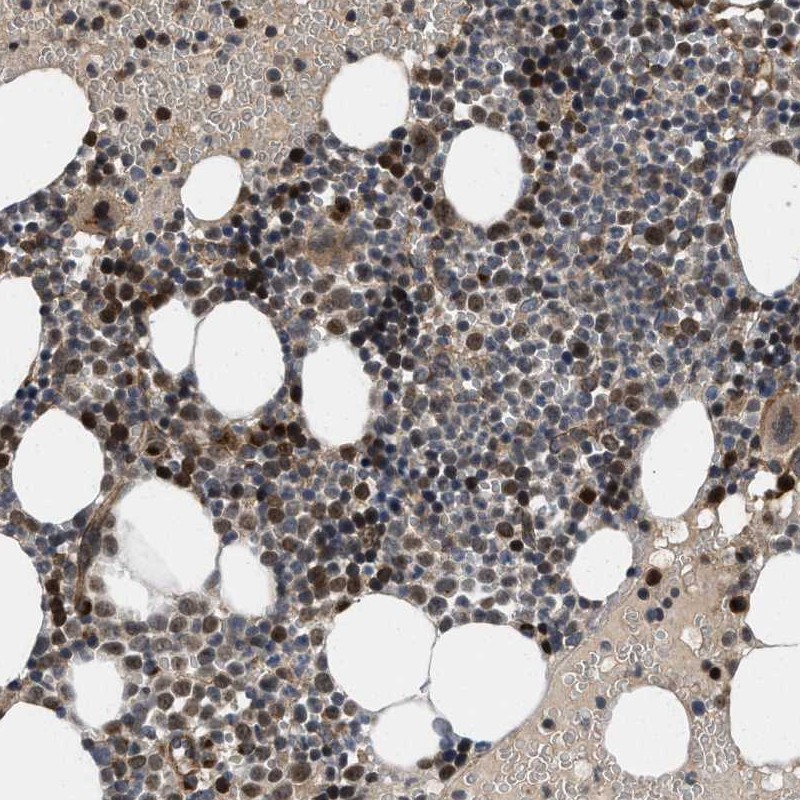

Immunohistochemical staining of human bone marrow shows distinct positivity in bone marrow poietic cells.